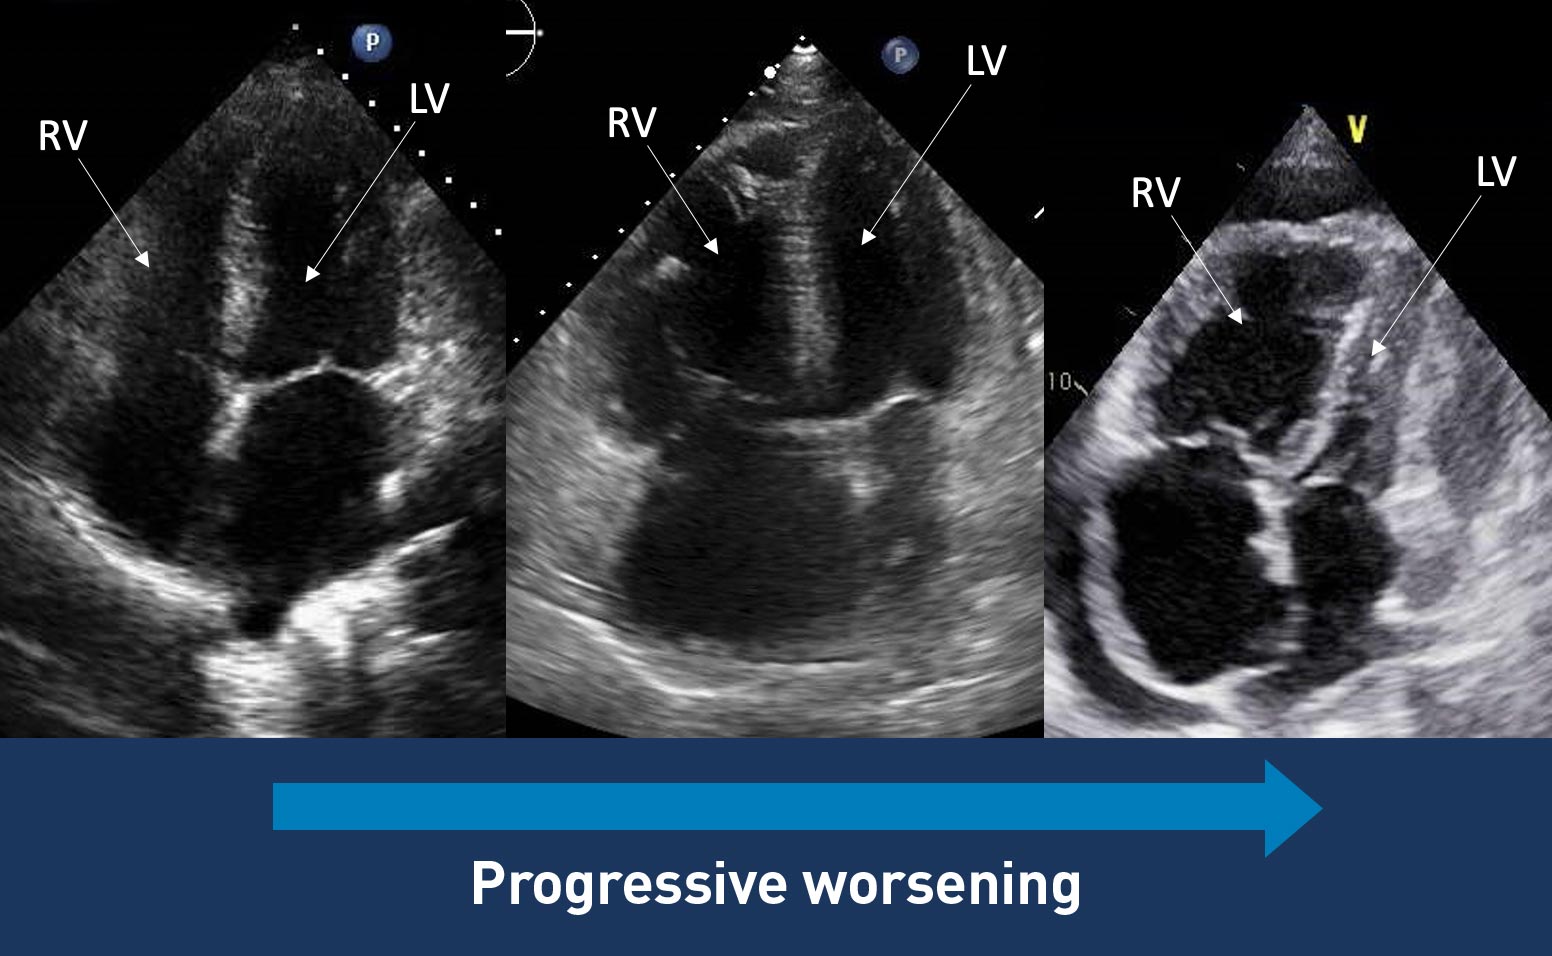

Echo images may suggest PAH

These Echos show the progressive dilation of the RV and RA in PAH.

In end-stage PAH, the RV may cause the interventricular septum to bow outward and compress the LV.

Other signs of RV dysfunction that can be found on Echo include1,12,13:

Echo of the heart that the progressive dilation of the RV and RA in PAHImages courtesy of Anjali Vaidya, MD, FACC, FASE, FACP. Pulmonary Hypertension, Right Heart Failure & CTEPH Program, Temple University Hospital.